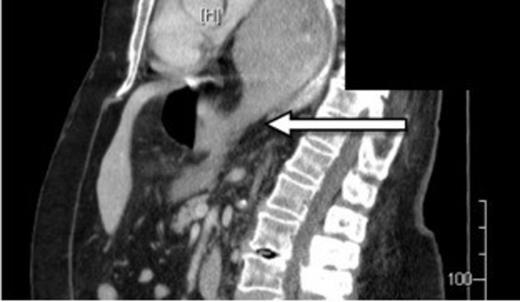

A 73-year-old Caucasian woman presented to the emergency department with 2-day history of vomiting and vague abdominal pain. Her background history included asymptomatic hiatus hernia, morbid obesity (BMI of 35.7), polymyalgia rheumatica, previous laparoscopic cholecystectomy, hypercholesterolaemia and hypertension. Regular medications included prednisone, amlodipine and cilazapril. On presentation she was tachycardic at 110 beats/min with otherwise normal vital signs. Her abdomen was generally tender but without any localised peritonism. Initial laboratory investigations on admission showed a leukocytosis (WCC of 13.8 x 109/L). Routine X-ray (figure 1) and subsequent (CT) scan (figure 2) both revealed a large strangulated paraoesophageal hernia. Radiographic changes (figure 3) were seen with gas within stomach wall, suggestive of gastric necrosis.

CT showing a large strangulated paraoesophageal hernia (arrow) within the thoracic cavity